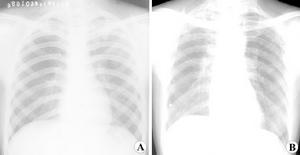

1.胸部X線檢查是肺膿腫的主要診斷方法。由於膿腫有向不同葉蔓延的特點,可波及多葉甚至全肺。但如一開始就發生在上述以外的部位,要懷疑有特殊的病因,如腫瘤堵塞性膿腫或肺囊腫感染等。肺膿腫在各不同階段病理改變很大,X線也有很大不同。急性期(在1周內)為大片緻密模糊陰影,按葉段分布呈楔形,尖向肺門,外側緊貼胸廓,縱隔或葉間胸膜面;在治療下,陰影改變較快。當膿腫與支氣管相通時,即出現空腔,由於引流支氣管多不通暢,加上體位因素,膿液不能完全排出,片上常見液平面。因壁厚,加上周圍仍有炎症,腔外有厚層,雲霧狀炎症浸潤影,慢性的周圍還有纖維化。空腔大小、形態不一,可呈圓形、橢圓形或不規則形,不少是多房的。經治療後如好轉,則空腔漸縮小、消失,留下纖維條索狀陰影及胸膜肥厚影。